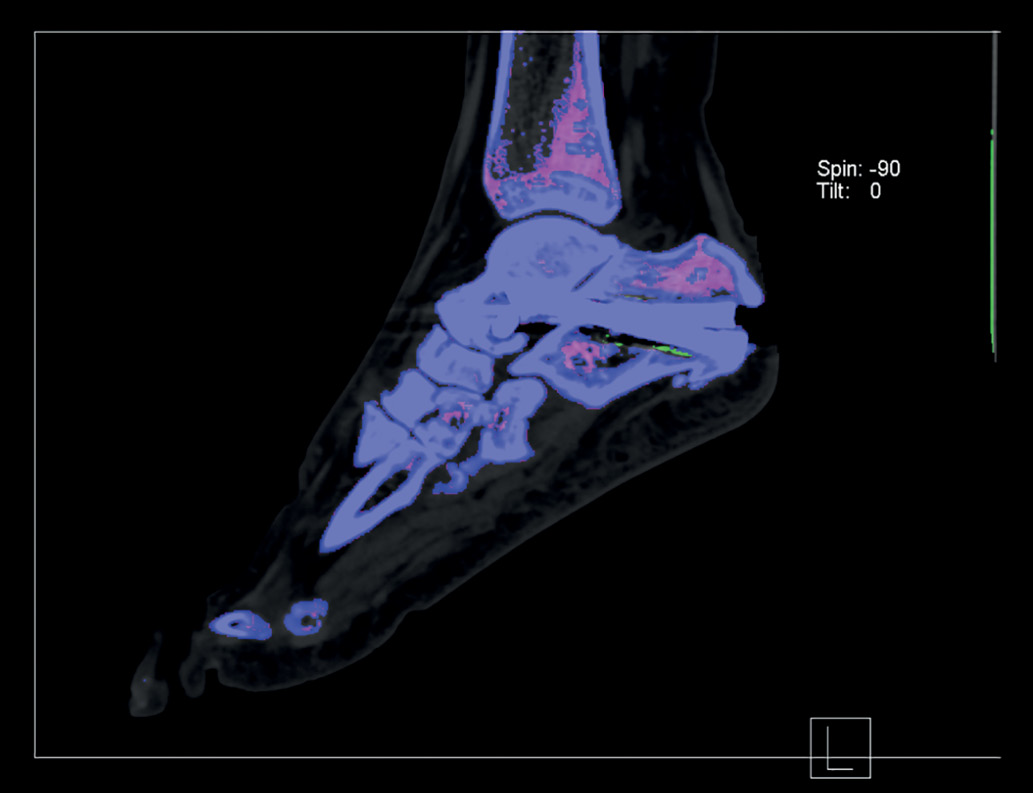

Пациентка повторно обратилась в ФГБНУ «Научно-исследовательский институт ревматологии им. В.А. Насоновой». При осмотре выявлялась болезненность в таранно-пяточных, 1-х плюсне-фаланговых, 2–4-х пястно-фаланговых и лучезапястных суставах. По данным анализов крови отмечено персистирование гиперурикемии (мочевая кислота сыворотки крови 429 мкмоль/л), маркеры острой фазы воспаления оставались в пределах нормальных значений. Проведена диагностическая пункция 1-го плюсне-фалангового сустава справа, однако кристаллы в синовиальной жидкости обнаружены не были. УЗИ также не выявило признаков депонирования кристаллов. В качестве дополнительного метода визуализации использована двухэнергетическая компьютерная томография (ДЭКТ), посредством которой выявлены депозиты кристаллов моноурата натрия в таранно-пяточном суставе левой стопы (рис. 1).

Рисунок 1. Двухэнергетическая компьютерная томография стоп пациентки С.

Примечание. Полученные при двухэнергетической компьютерной томографии данные отображаются в виде трехмерной модели c цветовым кодом. Отложение кристаллов моноурата натрия показано зеленым цветом, визуализируется в таранно-пяточном суставе левой стопы. Синим цветом обозначена кортикальная кость, фиолетовым — трабекулярная.

Figure 1. Dual-energy computed tomography of the feet of patient S.

Comments. Data obtained from dual-energy computed tomography is displayed as a three-dimensional model with a color code. The deposition of monosodium urate crystals is shown in green, visualized in the talocalcaneal joint of the left foot. Blue indicates cortical bone, purple indicates trabecular bone.

Таким образом, единственным диагностическим методом, входящим в классификационные критерии подагры и рассматриваемым как потенциально важный для диагностики болезни депонирования кристаллов пирофосфата кальция, оставалась ДЭКТ [18][28]. Для выявления отложений кристаллов пирофосфата ДЭКТ более чувствительна, но менее специфична в сравнении с рентгенографией [29]. Однако в отношении кристаллов моноурата натрия ДЭКТ обладает более высокой чувствительностью (90,4%) и специфичностью (74,5%). Визуализация кристаллов моноурата натрия по данным ДЭКТ в совокупности с другими признаками подагры увеличивает чувствительность действующих критериев диагноза подагры ACR/EULAR 2015 г. до 100% [30]. В случае пациентки С. результаты ДЭКТ стоп выявили отложения кристаллов моноурата натрия в таранно-пяточном суставе (рис. 1), то есть именно там, где определялись признаки артрита по данным сонографии.